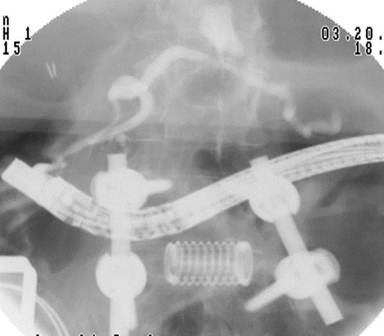

An additional two ports were placed in the right side; a 10/12-mm port in the subcostal position and a 5-mm port approximately 8 cm inferior to this. Since it was difficult to determine which limb was the afferent limb, a pediatric colonoscope was inserted transorally while observing intra-abdominally. The biliopancreatic limb was then identified. Following this, the bowel was easily drawn up to the abdominal wall through the right subcostal laparoscopic port. A longitudinal enterotomy was performed and tacked to the skin in the right subcostal area using four 3-0 silk sutures. A therapeutic-channel video duodenoscope (TJF-160VF, Olympus Corporation, Center Valley, PA, USA) was introduced into the enterotomy and advanced to the level of the major papilla, which was only approximately 20 cm from the enterotomy. Using portable C-arm fluoroscopy the pancreatic duct was easily cannulated and pancreatography was performed. The main duct was without obvious stricture. Extravasation of contrast was seen at the mid pancreatic duct (Figure 2). A hydrophilic guidewire was advanced beyond the leak to the tail of the pancreas. A 7-French, 12-cm pancreatic duct stent was placed across the leak (Figure 3). A pancreatic sphincterotomy was performed using a needle knife over the pancreatic duct stent. The bowel was then freed from the skin and the enterotomy was closed.

Figure 2. Radiographic image showing endoscope in position passed retrograde. A pancreatic leak is identified and is identical to the MRI. |